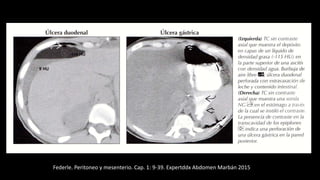

Federle. Peritoneo y mesenterio.

Cap. 1: 9-39. Expertddx Abdomen

Marbán 2015

Federle. Peritoneo y mesenterio. Cap. 1: 9-39. Expertddx Abdomen Marbán 2015